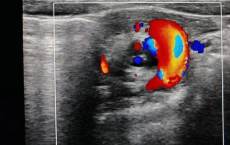

4岁女童反复阴道出血两月余,元凶竟是一枚玩偶纽扣!医生提醒:幼儿阴道异物需警惕,家长切勿自行处理

一名4岁女童因阴道内滞留一枚玩偶纽扣导致反复出血两月余,最终在桂林市妇幼保健院通过阴道内镜安全取出。医生提醒家长警惕儿童阴道异物,注意异常分泌物、出血、瘙痒等症状,切勿自行处理,应尽早就医,并加强监护与性教育,预防为主。